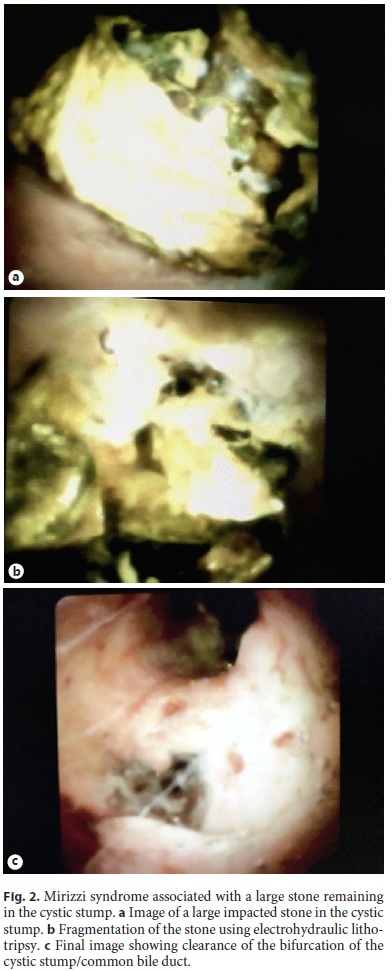

Of the 14 patients with difficult biliary stones, 12 patients (85.7%) had stones in the common bile duct/common hepatic duct and 2 patients (14.3%) had a single stone in the cystic stump (median diameter 10.5 mm; range 1112) (Fig. 2). In total, the 14 patients had a median number of 2 biliary stones (range 14) with a median diameter of 17 mm (range 1040). Of the 14 patients, 2 patients with stones in the common bile duct/common hepatic duct had an associated stone in the right hepatic duct (7 and 8 mm, respectively), which was also successfully submitted to cholangioscopy-guided lithotripsy.

Of the 14 patients, 1 patient with 2 stones of 20 and 40 mm was submitted to 3 sessions: in the first session, the patient was submitted to endotherapy with an EHL probe; after using two probes, none of the 2 stones was considered to be adequately fragmented, and the procedure was stopped and 2 biliary stents were left in the bile duct. In the second session, the patient was submitted to cholangioscopy-guided lithotripsy with holmium laser technol ogy with successful fragmentation of the stones and partial clearance of the ductal fragments (online suppl. Video S1; see http://www.karger.com/doi/10.1159/000488508 for all online suppl. Material). Between the second and the third session, 2 biliary stents were left in place, and in the third session the patient was submitted to treatment with conventional extraction devices including mechanical lithotripsy and achieved ductal clearance, which was only determined by an occlusion cholangiogram. This patient, with 90 years of age and a considerable number of comorbidities, had previously been submitted to several ERCPs with stent exchanges due to failed attempts at stone extraction.